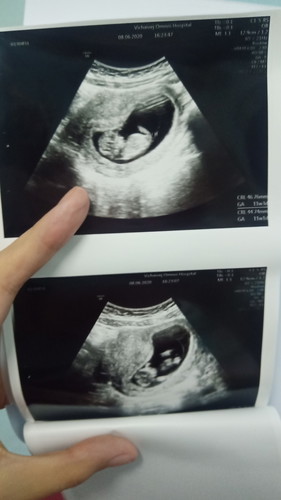

มีใครได้รูปอัลตร้าซาว์ดมาแล้วนั่งดูนั่งจ้องทั้งวันบ้างค่ะ มีความสุขมากเลย เด็กจิ๋วของแม่ 11 Week + 3 days